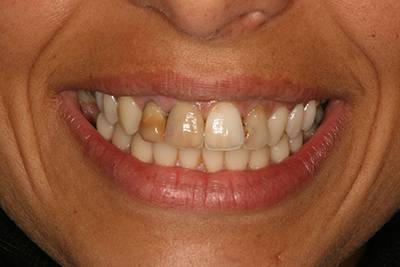

11. eset

27 éves páciensünk egész életében rettegett a fogorvosi beavatkozásoktól. Az összes foga elszuvasodott. A legkárosodottabb fogak gyökérkezelése és a szuvasodásainak megszűntetése után 26 fémkerámia koronát kapott a páciens. Erre a kezelésre is nagyon büszkék vagyunk. 2 hét leforgása alatt sikerült jelentős mértékben javítanunk a páciensünk mosolyán, önbizalmán és mióta velünk talalákozott, már a fogászati kezelésektől sem fél annyira!